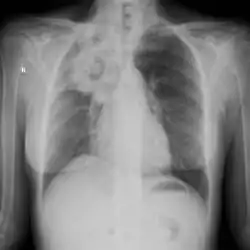

| Chest X-ray: widespread rounded lung nodules throughout both lungs | |

The extent of infection may be seen on X-ray or CT scan. On chest X-ray and CT, pulmonary aspergillosis classically manifests as a halo sign, and later, an air crescent sign.[21]